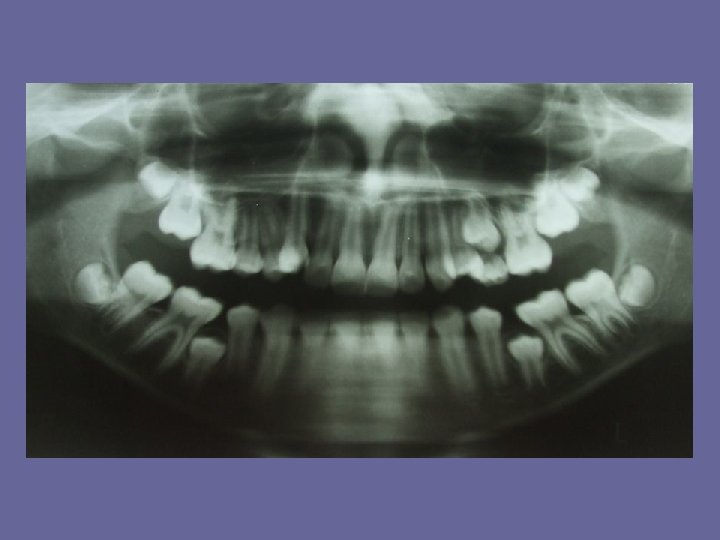

REPLACEMENT OF THE TEETH The eruption can be divided into periods: 1. The first period means a replacement of incisors, after which a break (usually 2 years) follows. 2. At the age of 10 -12 years the second period is performed. So the canines and premolars erupt.

ERUPTION OF THE FIRST PERMANENT MOLARS The stage of first permanent molars relationship formation is the most important stage of replacement. In normal occlusion, the anterior buccal cusp of upper first permanent molar should occlude with intercuspal ( buccal ) groove of lower first permanent molar. This relationship can be achieved in several ways.

ERUPTION OF THE FIRST PERMANENT MOLARS • at the end of dental arches a negative step is present ( when the upper second deciduous molar is as wide as lower ). So the first permanent molars are guided into right cuspal relationship.

ERUPTION OF THE FIRST PERMANENT MOLARS • a negative step may be present as a result of mesial drift of lower deciduous molars and closure of the lower primate spacing.

ERUPTION OF THE FIRST PERMANENT MOLARS • the second deciduous molars are flush distally, the first permanent molars are guided into a cusp-to-cusp relationship by their distal surfaces. • mesiodistal width of the permanent canines and premolars is usually less than of the deciduous canines and molars. The surplus space is greater in mandible. Thus when the second deciduous molars are shed the greater leeway space in the lower arch allows the lower first permanent molars to move forwards into a correct cuspal relationship with the upper.

ERUPTION OF THE FIRST PERMANENT MOLARS The order of eruption is important (the lower molar must be replaced before the upper )

ERUPTION OF THE FIRST PERMANENT MOLARS • if there is enough space, the maxilla and mandible are large, the right relationship of the first molars can be achieved • the bad situation is, if the lower second deciduous molar is too wide in relation to upper or there is a class II relationship and the positive step is present.